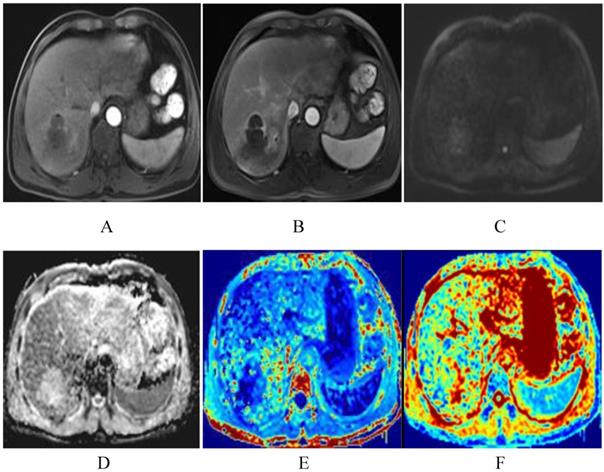

Figure 7

The patient was a 51-year-old man with HCC before TACE. The lesion of the right liver presents significant enhancement of heterogeneity in arterial phase, and decrease enhancement in venous phase, and shows as high DWI signals (A-C). The lesion shows low-signal-intensity in ADC and MD map, higher signal intensity compared with that of liver parenchyma in kurtosis map. The ADC, MD and MK values were 0.89×10-3mm2/s, 1.45×10-3mm2/s, 0.85, respectively (D-F).

J Cancer Image